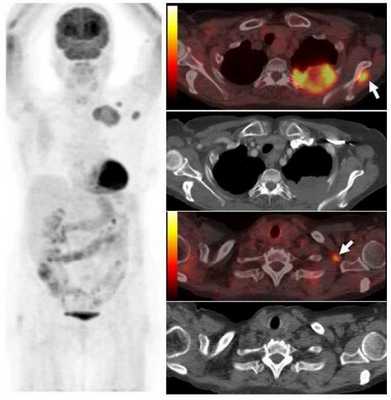

Опухоль левого легкого с частичным некрозом и деструкцией ребер. Визуализируются два метастаза в подключичных лимфоузлах и в мышцах (стрелки), которые на КТ не видны. Необходимо выполнить трансторакальную биопсию той части опухоли, которая расположена в периферических отделах, чтобы получить образец жизнеспособных тканей.